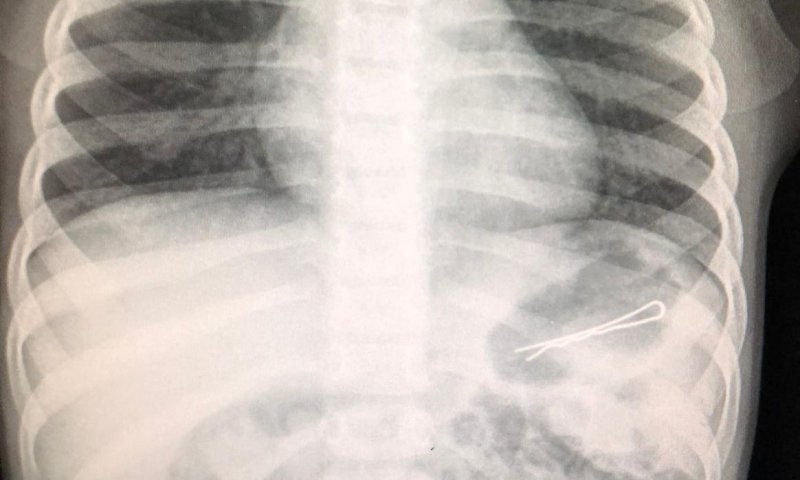

חייו של פעוט בן 3 ניצלו השבוע, לאחר שהובא למרכז הרפואי זיו כשבבטנו נמצאה סיכת ראש באורך 6 ס"מ אותה בלע.

בעקבות קושי בנשימה בוצע צילום רנטגן ובו נראתה בבירור הסיכה שהחלה לעבור בשער הקיבה ולכן היה צורך בביצוע גסטרוסקופיה, תוך החדרת צינור מהגרון לקשת התריסריון ושליפת הסיכה בזהירות רבה, כיוון שאחד מצדדיה חד.

ד"ר ביאן הינו אמר: "ילדים בולעים גופים זרים שונים, אבל יש כמה שדורשים התייחסות מיוחדת והוצאה אנדוסקופית מיידית כשהם בטווח השגה, כמו סוללות וכפתור בושט. במקרה הזה, הפעוט בן ה-3 בלע סיכת ראש באורך 6 ס"מ שנתקעה בקשת התריסריון ולכן נדרשה הוצאה אנדוסקופית בהרדמה כללית בחדר. לאחר שהילד התאושש וחש בטוב, הוא שוחרר לביתו".